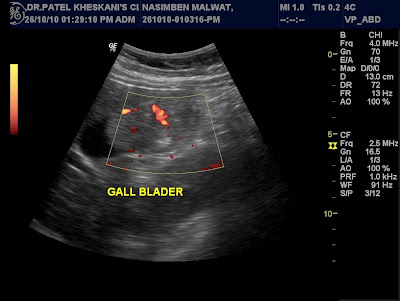

Ultrasonography shows normal upper abdomen sonography.

Colour doppler study shows colour flow in the feotal heart.